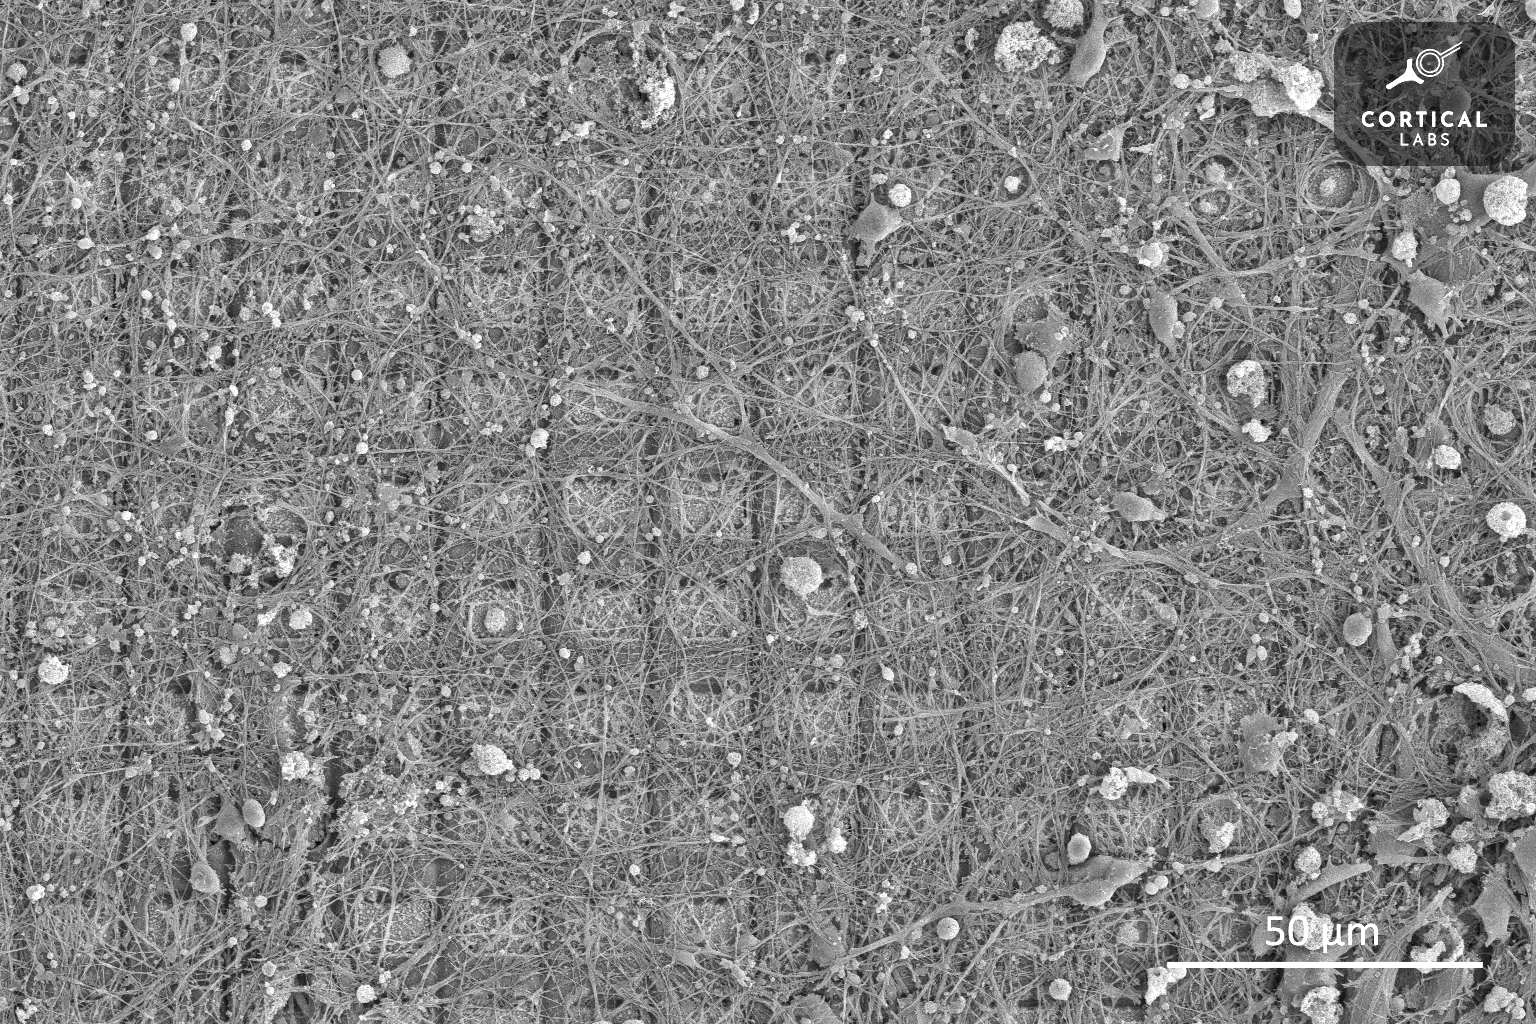

An anonymous reader quotes a report from Interesting Engineering: Imagine exploring the intricate world within a single cubic millimeter of human brain tissue. It might seem insignificant, but within that tiny space lies a universe of complexity -- 57,000 individual cells, 230 millimeters of blood vessels, and a staggering 150 million synapses, the junctions where neurons communicate. Envision a piece of brain tissue roughly half the size of a rice grain but magnified to reveal every cell and its web of neural connections in vivid detail.